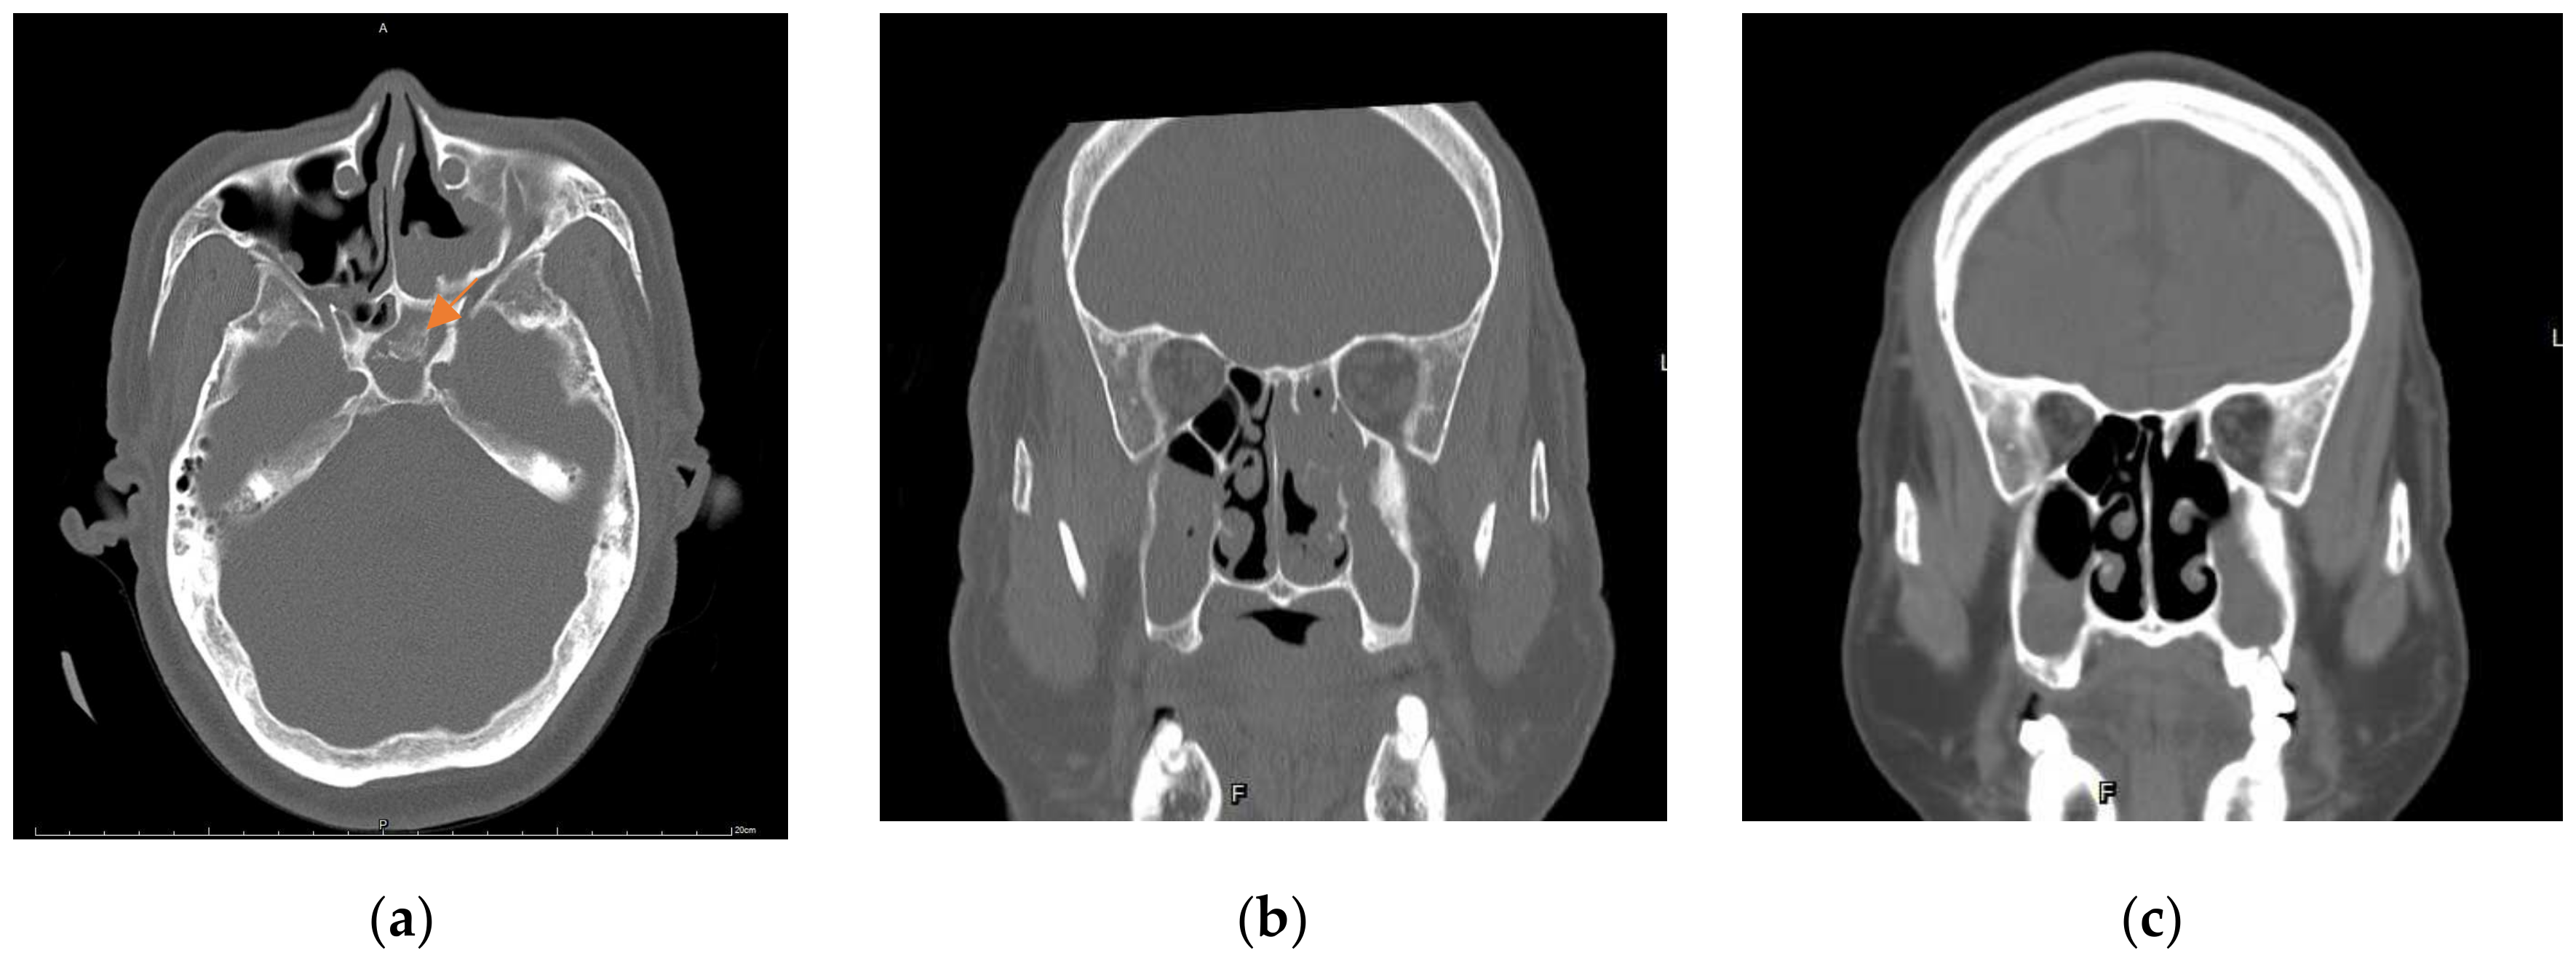

2. Case Report